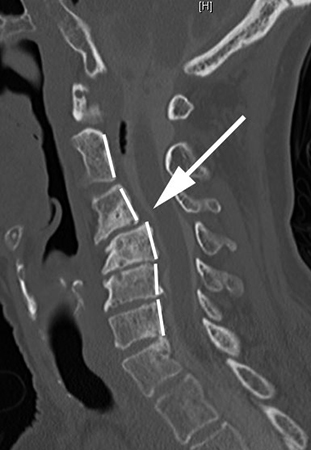

Подтвердить или опровергнуть диагноз позволяет рентген. Он определяет стадию развития заболевания и причину его возникновения. Более информативными методиками считается МРТ или КТ, но их назначают в отдельных случаях для получения развернутой картины состояния пациента.

Рентгеновский снимок является надежным способом обнаружить патологию

Диагностировать клиновидное смещение можно с помощью рентгенографии поврежденного отдела в боковой и прямой задней проекции. На ранних стадиях лучше всего изменения зафиксировать при помощи томографии. Это дает возможность диагностировать трещину позвонка, грыжу, изменения в губчатом теле позвонка, остеопорозные изменения.